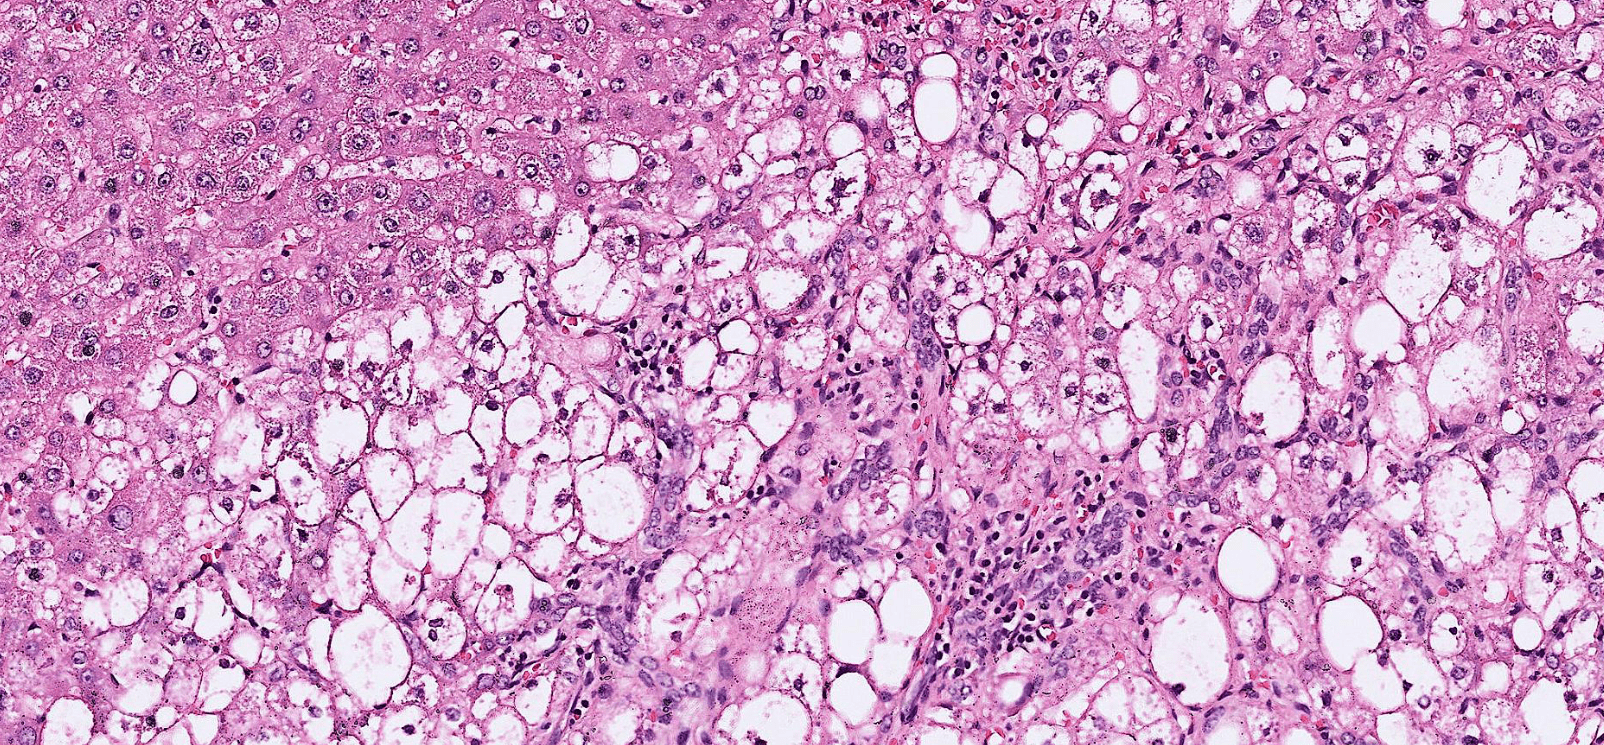

breast cancer

dyslipidemia

hepatocellular carcinoma